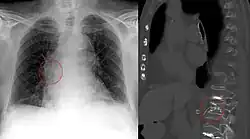

- Lungenembolie (= venöse Embolie): Der Embolus stammt aus Körpervenen und verstopft nach Passage der rechten Herzhälfte Lungenarterien.

- Arterielle Embolie: Embolus stammt aus dem Herzen oder großen Arterien und verstopft Arterien (z. B. Schlaganfall, Herzinfarkt, Mesenterialinfarkt, Verschluss einer Beinarterie, Retinaler Arterienverschluss)